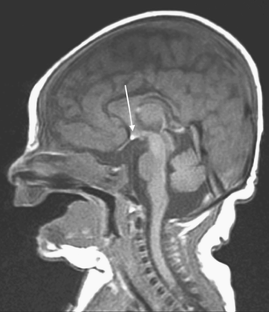

Patients with congenital hypopituitarism might have the classic triad of pituitary stalk interruption syndrome, which consists of: (1) an interrupted or thin pituitary stalk, (2) an absent or ectopic posterior pituitary (EPP), and (3) anterior pituitary hypoplasia or aplasia.

Fig. 1